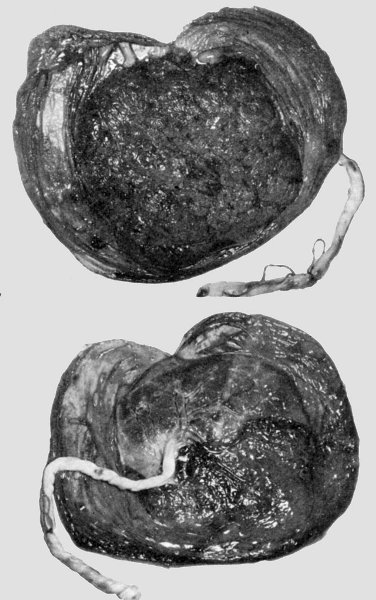

3. Placenta fenestrata. The central area of the placenta has a distinct... | Download Scientific Diagram